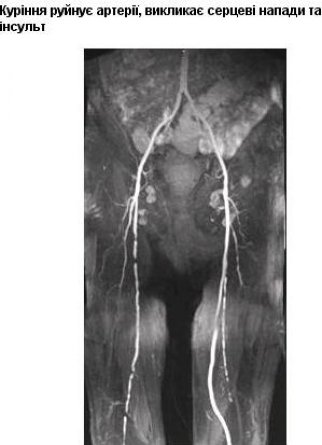

Якими малюнками на пачках цигарок лякатимуть курців. ФОТО

Всі упаковки тютюнових виробів в Україні від 4 жовтня повинні виготовлятися з фотоілюстраціями із зображеннями хвороб, які викликає куріння.

50% передньої частини пачки буде займати напис: "Куріння вбиває", а із зворотного боку на 50% розміститься графічне зображення з попереджувальним написом.

Всього буде використовуватися 10 варіантів графічних попереджень з відповідними коментарями.